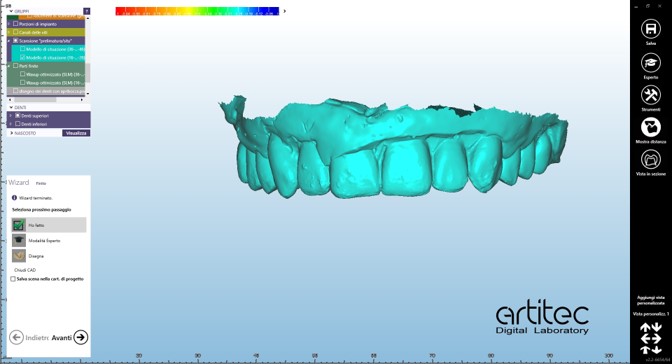

Nell’ultimo incontro prima della finalizzazione delle protesi si verifica la passività ed il corretto accoppiamento protesico di barre in CrCo laser melting sulla base delle quali successivamente sono realizzate le barre in fibra di vetro continuo stampata in 3D. (fig.16-21)

Le protesi definitive su barra in fibra di vetro stampata in 3D sono consegnate nell’ultimo appuntamento. Le viti di ritenzione sono serrate a 25ncm come da indicazione del produttore e i fori passanti sono chiusi con PTFE e composito. L’occlusione viene ricontrollata con carta di articolazione e i ritocchi sono eseguiti come ultima fase di consegna. Alla paziente sono fornite le prime istruzioni di igiene orale domiciliare. (fig. 22-28)

foto 22 produzione barra in fibra di vetro continuo stampata in 3d

foto 23a consolidamento rinforzo in fibra di vetro continuo stampata in 3d a link implantari

foto 23b fasi di lavorazione e stratifica materiale

Le tecniche implanto-protesiche descritte in questo case report hanno dimostrato come la programmazione digitale con protocollo di lavoro Toronto monomassa e composito e rinforzi dentali stampati in 3D permetta una riabilitazione protesica completa e funzionale. L'utilizzo di un flusso di lavoro digitale per la riabilitazione protesica offre numerosi benefici per il paziente e per il professionista. Il primo beneficio è la precisione nella pianificazione del trattamento: la possibilità di utilizzare scanner intraorali e software di previsualizzazione digitale consente di ottenere una rappresentazione precisa della situazione clinica e di pianificare l'intervento in modo preciso e mirato. Inoltre, l'utilizzo di un protocollo di lavoro basato sull’impiego di strutture di rinforzo in fibra di vetro stampata in 3D permette di integrare lavorazioni digitali in un flusso di lavoro più rapido e meno soggetto a potenziale variabilità introdotta da eventuali errori dell’operatore. Infine, l’utilizzo di queste tecnologie permette una maggiore efficienza e tempestività nel trattamento, garantendo una maggiore sicurezza e qualità delle protesi.